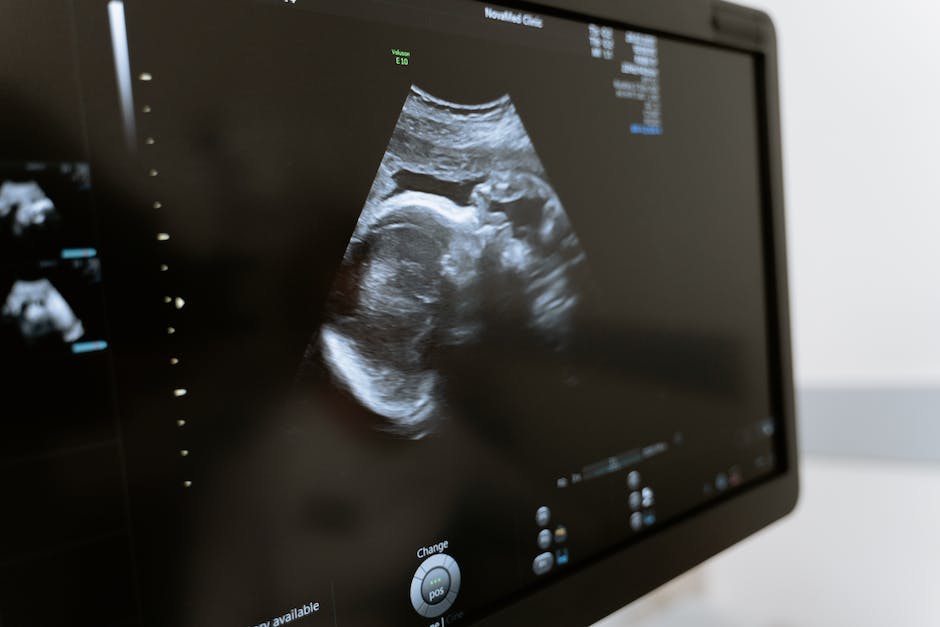

3. 갑상선 초음파

갑상선 초음파는 갑상선의 크기와 형태, 덩어리의 유무 등을 확인하기 위해 사용됩니다. 이는 갑상선 암의 초기진단과 갑상선 결절의 평가에 유용합니다. 검사를 통해 소량의 신체 내부 변화를 사전에 확인할 수 있기 때문에 매우 중요하여 정기적 검진을 추천합니다.